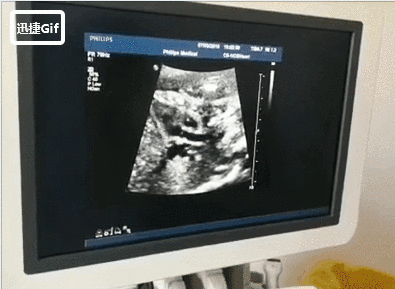

显示的是断面图像。何为断面图像?就好像把西瓜切开,你在屏幕上只能看到“西瓜”的切面(断面),一般挑西瓜,到切开之后,已经可以断定这个西瓜好不好了。

对于医生来说,二维超声和CT、磁共振一样,都是一张一张断面图像,医生凭大脑重建成立体图像,就能够判断胎儿的健康状况了。而三维、四维则是更具象的完整图,其实很多时候,都是为了不懂医学的家长看的。